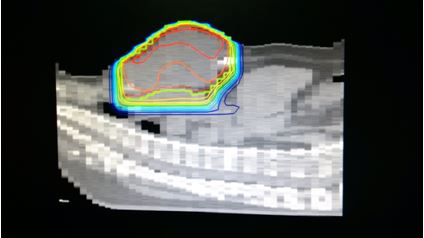

• Bệnh nhân được xạ trị gia tốc lần hai, 18Gy, phân liều 4,5 Gy/buổi x 4 buổi